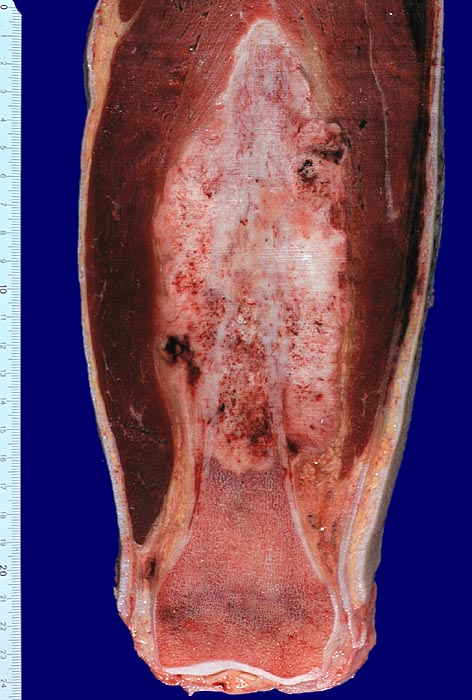

PathoPic – image database / PathoPic ID 3240 - Osteosarkom

Osteosarkom

maligner Tumor

Knochen, Femur

Tumor an klassischer Lokalisation im Bereich des distalen Femur. Das weissgraue Tumorgewebe wächst infiltrativ und destruktiv. Es füllt den Markraum und infiltriert durch den Cortex unter Abhebung des Periosts in die Weichteile.

Makroskopie